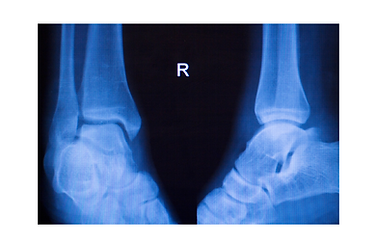

Fracture

Fractures to the distal fibula are common in a lateral ankle injury. Depending on the area of fracture, the management may differ.